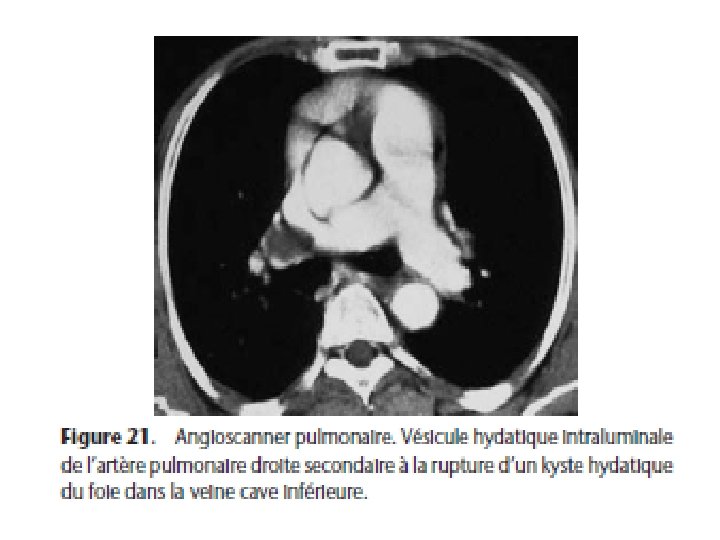

Kystes hydatiques multiples • Infestation itérative : opacités de dimension variée • Hydatidose secondaire: rupture d’un kyste hydatique préexistant (cycle court) RX= kyste primitif rompu et kystes secondaires en nombre varié et de dimensions variées Rupture du KH du foie dans la VC ou du KH du myocarde dans le cœur droit entraine une « miliaire » hydatique qui évolue inexorablement vers la mort